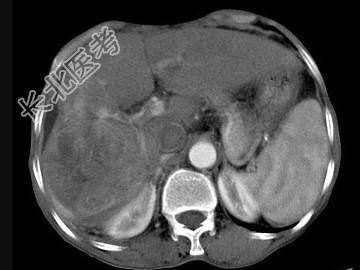

- 单项选择题女,40岁, 有口服避孕药史,肝区疼痛、腹部包块, AFP阴性,CT扫描如图, 最可能的诊断是

A、肝细胞腺瘤

B、肝再生结节

C、结节性肝癌

D、肝右叶巨块型肝癌

E、肝黄色肉芽肿